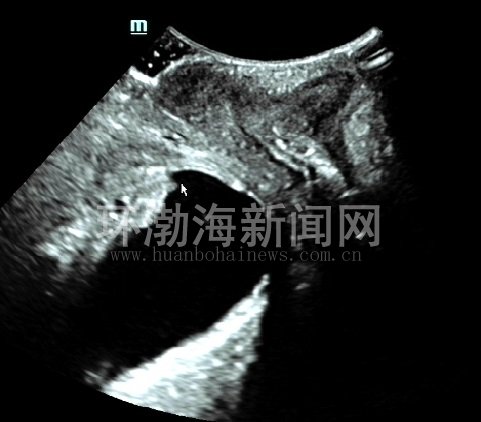

患者,张女士,30岁,阴道分娩1次,产后7个月,因咳嗽、大笑、打喷嚏时漏尿,产后便秘等症状到该院就诊。经该院盆底超声检查发现,在完成最大乏式动作(Valsalva)时膀胱内口呈锥形扩张,直肠前壁向后膨出;肛门内外括约肌完整,静息状态时肛提肌裂孔的三维图像呈规则的菱形,前、中及后三腔室结构完整紧凑,最大乏式动作时肛提肌裂孔面积稍有增大,但结构仍然完整紧凑。这样,一下子找到了过去不算病的“病根”,到相关科室对症治疗及解决了多日的“尴尬”。

图1:膀胱内口呈锥形扩张